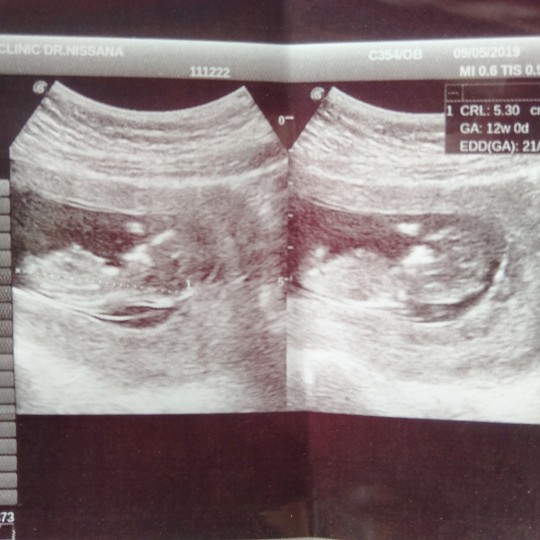

12Wค่ะ

3เดือนแล้วค่ะ..เริ่มเห็นแขน ขา บ้านใหนเหมือนกันมั๊ยค่ะ???3เดือนเห็นชัดขนาดนี้เหมือนกันรึป่าวค่ะ

,ตอน12วีคค่ะ ตอนนี้15+3ค่ะ